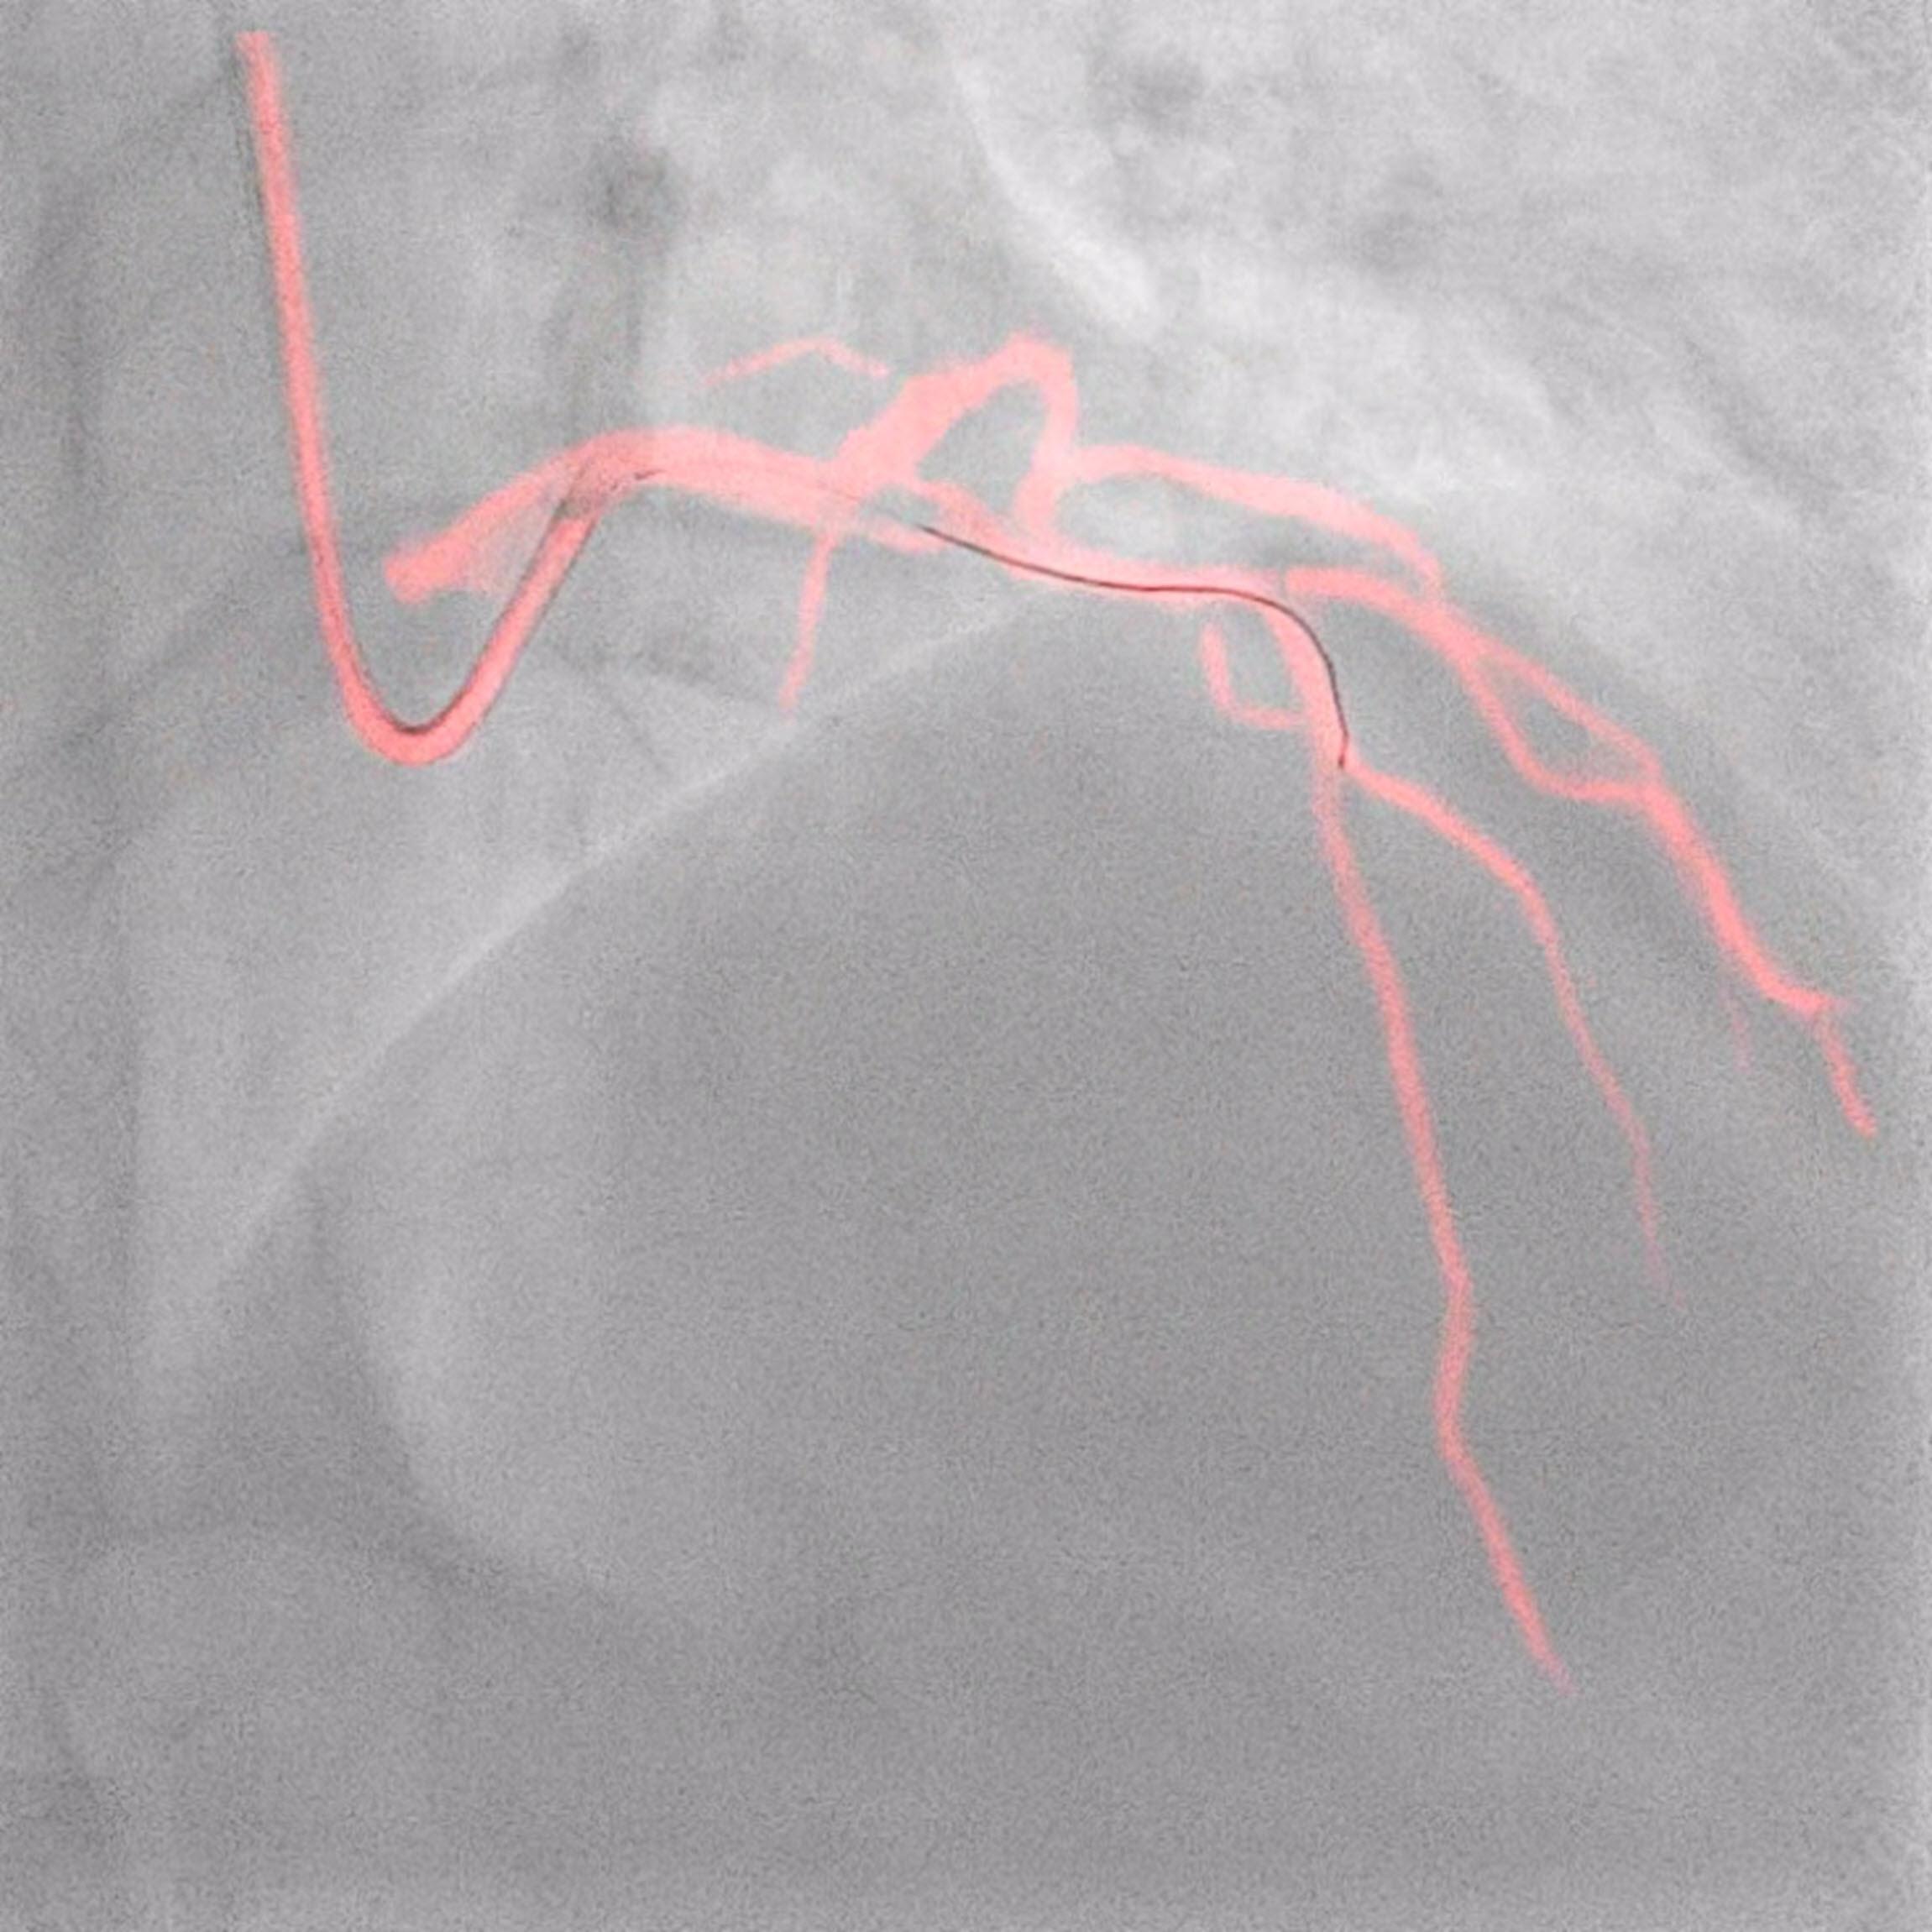

Những cải tiến nổi bật từ danh mục tim mạch của Philips được trưng bày tại EuroPCR bao gồm Hệ thống chụp mạch can thiệp của Philips – Azurion , Nền tảng ứng dụng can thiệp của Philips – IntraSight, bên cạnh các giải pháp trực quan như Hệ thống dẫn hướng chính xác của Philips – SyncVision, Bản đồ vận động mạch vành của Philips (DCR), công cụ hòa hình Angio và hình ảnh siêu âm 3D – EchoNavigator , Pressurewire thăm dò sinh lý mạch máu– OmniWire và Catheter tạo ảnh siêu âm trong lòng mạch (IVUS). Bên cạnh đó, Philips sẽ giới thiệu các giải pháp khoan cắt mảng xơ vữa, chẳng hạn như bóng quấn lưới kim loại RX PTCA – AngioSculpt Evo và catheter khoan phá mảng xơ vữa động mạch vành bằng laser – ELCA.

Các buổi đào tạo trực tiếp do chuyên gia hướng dẫn, hội thảo chuyên đề và trình chiếu tại gian hàng sẽ cung cấp cho các bác sĩ và phương tiện truyền thông cái nhìn sâu sắc về những phát triển mới nhất trong việc tối ưu hóa các quy trình ULC-PCI. Philips cũng sẽ tổ chức Phiên mô phỏng IVUS để nhận biết các tổn thương vôi hóa khác nhau bằng siêu âm nội mạch (IVUS) và chụp cắt lớp quang học. Tại Phiên hội thảo vệ tinh của Philips, khách tham quan có thể tìm hiểu thêm làm thế nào các giải pháp của Philips hỗ trợ các bác sĩ can thiệp trong việc giảm thiểu lượng chất cản quang cho bệnh nhân và bác sĩ, đồng thời thực hiện các quy trình can thiệp một cách rõ ràng và tự tin bằng cách sử dụng các giải pháp như IVUS, iFR , FFR và laser, cải thiện trải nghiệm trong chăm sóc tim mạch cả cho nhân viên và bệnh nhân.